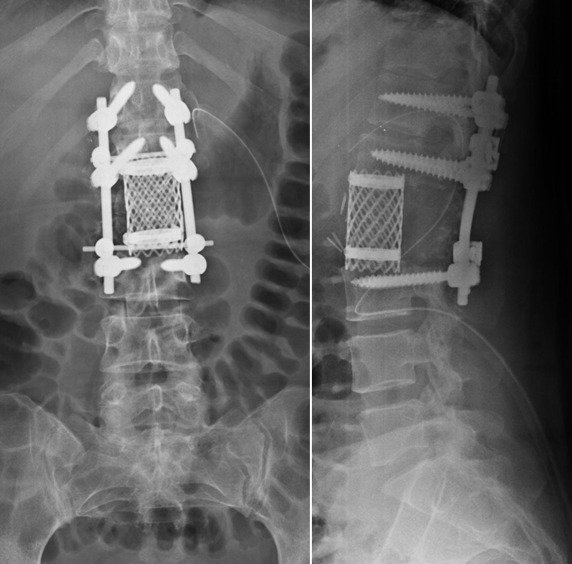

Clinical case: A 40-year-old woman diagnosed with low-grade spinal chondrosarcoma underwent a total en-bloc spondylenctomy (TES) surgery. This technique required a wide resection, anterior reconstruction with a titanium mesh cage (TMC), and posterior stabilization. For several years a favorable clinical outcome was achieved. After 10 years of follow-up, the patient developed acute non-traumatic low back pain without neurological repercussions. The images confirmed a rupture of the titanium cage. After ruling out tumor recurrence, the patient went through spinal instrumentation revision.

Conclusion: Isolated TMC rupture is a rare event scarcely reported in the literature. There is a strong recommendation to instrument two levels proximal and distal to the bone defect in 360° reconstructions after a TES. Stability had likely been lost over the years due to the slow resorption of the bone graft. We consider necessary studies with a higher casuistry and level of evidence to analyze the contributing factors for the event of TMC rupture.